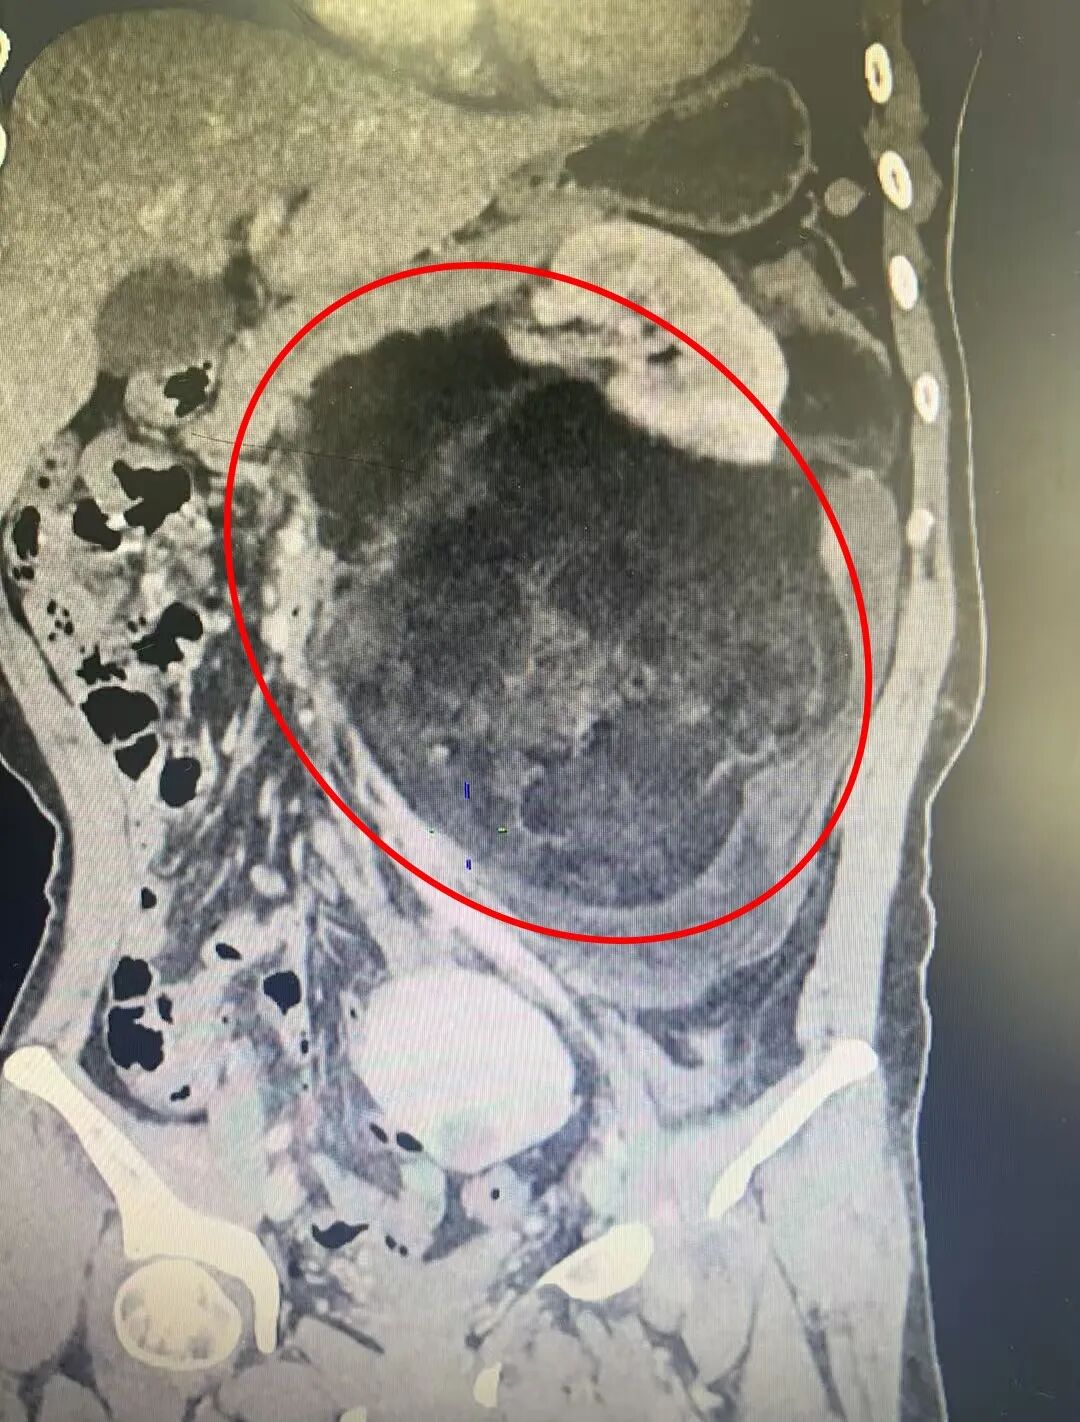

急诊科医生接诊后,病情比较特殊,第一时间向急诊科石聪辉主任汇报并为王女士安排相关重点检查。腹部增强CT检查后发现她左腹膜后有一个巨大占位性病变。病情特殊,急诊石聪辉主任立刻启动院前肿瘤多学科会诊机制,泌尿二科、普外科、肿瘤内科、放射科等科室专家共同评估病情,最终高度考虑“左腹膜后巨大肿瘤:脂肪肉瘤可能”,以泌尿外科病情为主,遂收入泌尿二科进一步诊治。

进一步检查确认,王女士的肿瘤长径接近30厘米,已越过腹正中线,和周围的胰腺、空肠、左肾、结肠及血管等脏器紧密粘连,分界不清。如此巨大的肿瘤,不仅手术切除难度极高,还可能在术中损伤周围重要脏器或血管,引发大出血等致命风险。

患者住院完善相关检查后,为确保手术安全,漳州第三医院副院长韩聪祥再次组织普外科、肿瘤内科、放射科、麻醉科、病理科等多学科专家进行术前多学科讨论。专家们反复分析影像学资料,精准评估肿瘤与周围组织的解剖关系,详细探讨手术中可能出现的情况及手术预案,最终制定出“经腹左腹膜后巨大肿瘤切除+左肾切除,备左半结肠切除”的个性化手术方案,同时敲定了详尽的术中应急处置方式,并与患者及家属进行详细的沟通解释,取得配合和理解。

手术当天,在韩聪祥副院长的带领下,泌尿二科团队与普外二科邹耀祥主任紧密协作,手术按既定方案有序推进。术中,医生们凭借丰富的临床经验和精湛的手术技巧,小心翼翼地分离肿瘤与周围脏器、血管的粘连。每一步操作都精准谨慎,既要避免损伤重要组织,又要确保肿瘤完整切除,整个过程如同在“雷区”中开辟通道。手术过程十分顺利,手术历时近4小时,出血约150ml,未损伤临近的重要脏器,也充分保护了结肠的血管,避免了再行结肠切除的损伤。这个长近30厘米的巨大肿瘤被完整切除,其体积堪比一个中等大小的西瓜。